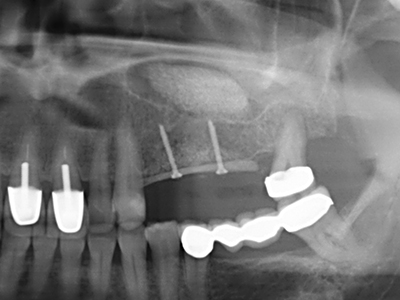

Bei der Knochenblockentnahme zeigen sich weitere Vorteile für die Piezochirurgie: Neben der bereits beschriebenen hohen Präzision bei der Osteotomie stellt sich gerade die Verwendung der dünnen Sägespitzen als besonders materialschonend heraus. Bei der Verwendung insbesondere von Lindemannfräsen sind mit deutlich höheren Entnahmeverlusten durch die dickere Instrumentenspitze zu rechnen (Lakshmiganthan, Gokulanathan et al. 2012). Die insbesondere bei retromolar entnommenen Blocktransplantaten notwendige basale Abtrennung wird durch speziell hierfür vorgesehene rechtwinklige Sägen erleichtert, so dass die Piezochirurgie als präzises, übersichtliches und sicheres Verfahren zur retromolaren Knochenblockgewinnung angesehen wird (Happe 2007) (Abb. 1-12).

Sollen chirurgische Eingriffe mit unmittelbarer Knochenbeziehung an empfindlichen Strukturen wie Blutgefäßen oder Nerven erfolgen, so bergen rotierende Instrumente ein erhebliches Potential an iatrogener Schädigung. Gerade bei Nervdarstellungen nach iatrogener Schädigung, oder aber im Zuge einer Nervlateralisation für resektive und rekonstruktive Eingriffe oder Implantatinsertionen können piezoelektronische Geräte hilfreich sein Knochendeckel zu präparieren und nervnahe Hartgewebsanteile zu entfernen (Abb. 17-20). Ein leichter Kontakt des Nervstrangs zur Piezospitze bleibt dabei in der Regel folgenlos – allerdings kann eine unvorsichtige Vorgehensweise mit sägeartigen Bewegungen bzw. Ansätzen bei noch vorhandener knöcherner Unterlage durchaus temporäre oder aber auch permanente Nervschädigungen verursachen. Das Risiko einer solchen Schädigung wird jedoch als wesentliche geringer eingeschätzt als unter Anwendung von Säge- oder Fräsinstrumenten (Pereira, Gealh et al. 2014).

Wie sich in der Vergangenheit gezeigt hat stellt prinzipiell jeder knochenchirurgische Eingriff eine mögliche Indikation für die Piezochirurgie dar. So lässt sich die Präparation des mobilen Segmentes bei der Distraktionsosteogenese (Abb. 23-25) und der Sandwichosteotomie mit speziellen Ansätzen bewerkstelligen, ohne die für den Erfolg beider Techniken essenzielle Blutversorgung des krestalen Anteils zu gefährden (Gonzalez-Garcia, Diniz-Freitas et al. 2008).

Für die Entnahme von Implantaten ist die Präparation eines vestibulären Knochendeckels möglich, der nach Entfernung der Implantatschraube refixiert wird und auf diesem Wege die Kontur des Alveolarfortsatzes erhält.